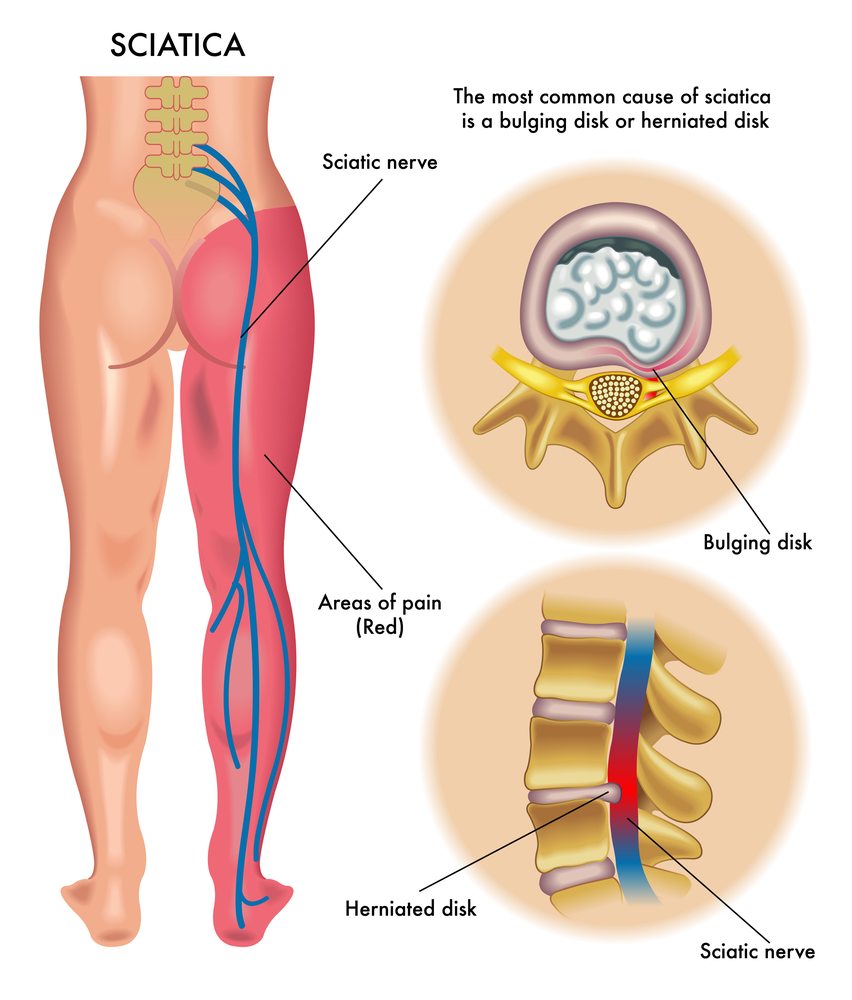

Non-surgical, natural relief for Arthritis, Cervical Spondylitis, Slip Disc, Sciatica, Gout, and Calcaneal Spur (heel pain). Get back to moving freely again.

Pain & Spine

Effective treatment for Cervical Spondylitis, Slip Disc, and Sciatica. Regain your mobility and live a pain-free life.

Slip Disc / Gout / Sciatica

स्लिप डिस्क / गठिया / साइटिका